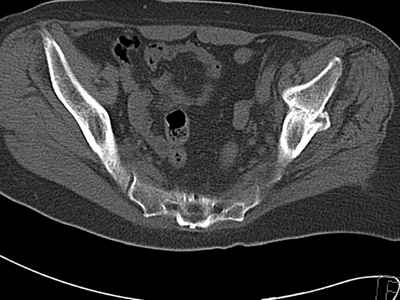

Уважаемые коллеги, возник вопрос по лечению нашей пациентки 60 лет. Около года назад множественная травма: в том числе Т-образный перелом вертлужной впадины. На сегодняшний день сращение отломков имеется на ограниченных участках, имеется дефект задней колонны вертлужной впадины. Движения неплохие, ходит с костылями, приступая на ногу. По мнению эдопротезистов при установке антипротрузионного кольца или октопуса не хватит костного материала и необходимо перед протезированием выполнить реконструкцию впадины, иначе чашка протеза неминуемо выпадет.Просьбы поделиться положительным и отрицательным опытом протезирования в подобных случаях.Возможно ли обойтись без реконструкции?Или лучше с ней?С уважением РАВ.

По моему мнению предварительну реконструкцию делать нет необходимости. Операцию надо выполнять одномоментно с пластикой вертлужной впадины. по поводу того, что не хватит головки. Да не исключено. Но ведь есть и другие материалы. Лучше при таком раскладе иметь в запасе замороженную головку. если нет возможности, как вариант два крыла подвздоной кости + хронос или его аналоги. По поводу выбора конструкции. Октопус в данной ситуации будет совсем не уместен, т.к. имеется дефект задней колонны вертлужной впадины. Да как конструкция октопус встанет не плохо. Но в функциональном плане не будет хорошей задне латерально и заднемедиальной точек опры впадины на период перестройки трансплатов. И по этому в данной ситуации более уместно кольцо Бурх(г)-Шнайдера с аналогичной пластикой, но возможнотью зафиксировать отломки задней колонны, крыши. Естественно цементная чашка с козырьком из кросс линк полиэтилена. Гололвка керамика, ножка бесцементная можно Цваймюллера или любой другой конструкции, они сейчас все хороши.

Основное внимание необходимо уделить стабильности костных фрагментов в зоне перелома вертлужной впадины. Если имеется нестабильность я предпочел бы Октопус для остеосинтеза и стабильности вертлужной впадины. Этот момент является основным для успешного протезирования.

Если впадина единое гнездо по окружности, достаточно антипротрузионного кольца или Буршнайдера.

Добрый день. Ваше наблюдение обнаружил только сегодня. Очень интересный случай. Надеюсь, не опоздал со своими предложениями. Считаю, сто можно обойтись без опорногот кольца. А пластика впадины нужна. Мы в подобных случаях помимо аутотрансплантатов используем гидроксилапатитную керамику в виде гранул. Результаты хорошие. Возможно при ревизии впадины окажется, что следует выполнить остеосинтез передней или задней колонн. Желаю успехов.